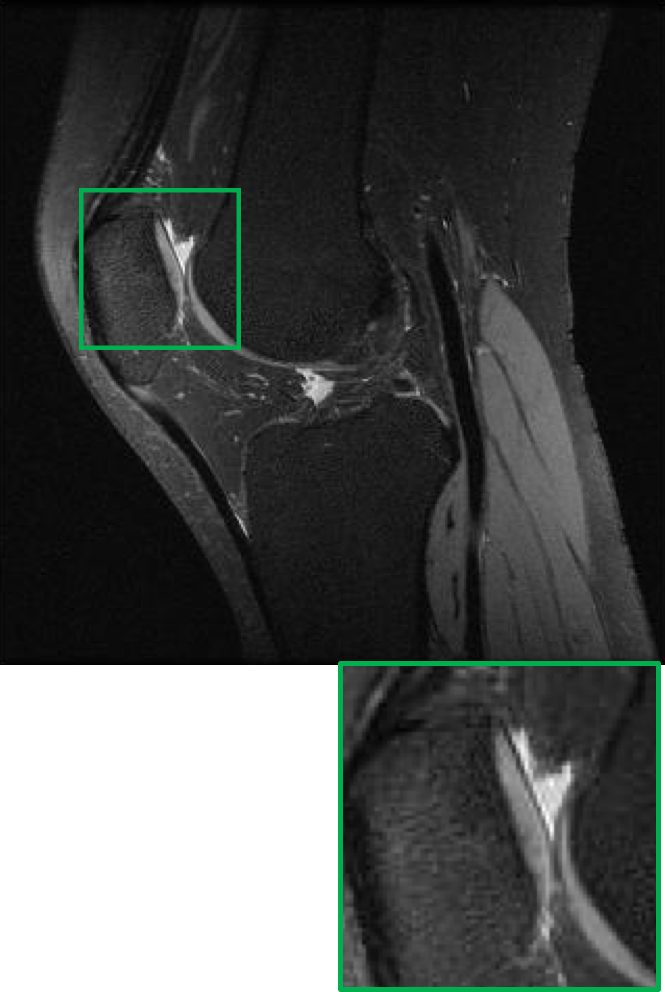

CS MR measurement matrix

LDAMP SURE was applied to CS-MRI reconstruction problem to demonstrate its generality and to show its performance on images that contain structures different from natural image dataset. We compared LDAMP SURE with state-of-the-art BM3D-AMP-MRI algorithm [16] for CS-MR image reconstruction along with TVAL3, BM3D-AMP, and dictionary learning method or DL-MRI [34]. Average image recovery PSNRs and run times are tabulated in Table 3. Figure 5 shows that our proposed method yielded state-of-the-art performance, close to the ground truth. The results reveal that proposed LDAMP SURE-T outperforms existing algorithms in all sampling ratios.

Ground truth

TVAL3

BM3D-AMP

DL-MRI

BM3D-AMP-MRI

LDAMP SURE-T